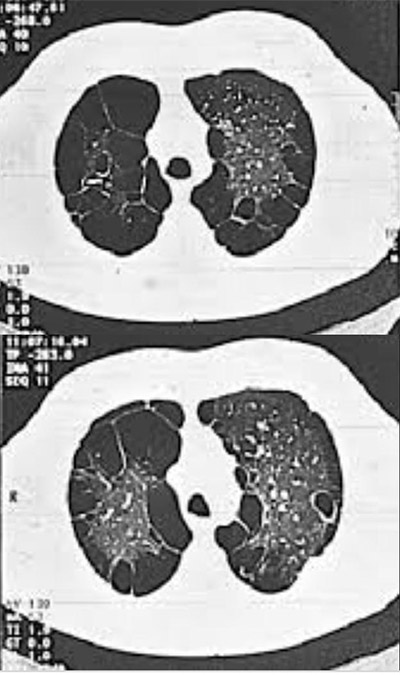

Saiba maisScreening de câncer de pulmão

Conheça o procedimento que rastreia o câncer de pulmão em pacientes assintomáticos